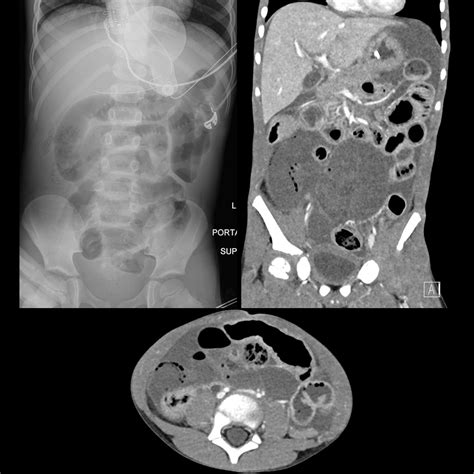

CT Scan Structural imaging of the abdomen Moderate (good for complications like obstruction)